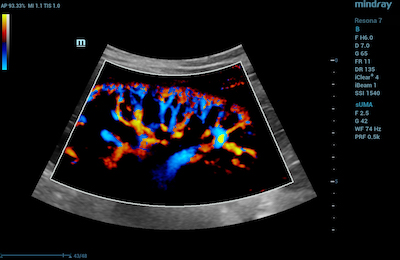

- Ultra Micro Angiography (UMA) is an innovative method of visualizing low-velocity micro-vascular flow states. UMA compensates for the limitations of traditional flow modes in detecting slow flow. It allows for visualization of the supply vessels surrounding diseased tissues, further enhancing diagnostic capabilities for lesion detection and characterization.

- Color UMA – UMA with a traditional color map overlay for improved sensitivity

Color Ultra Micro Angiography of Hepatic Vasculature